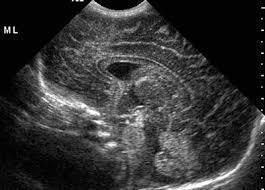

PEDİATRİK TRANSFONTANEL ULTRASON (BEYİN ULTRASONU)

Transfontanel ultrason yeni doğan bebeklerde sıklıkla kullanılmakla birlikte bebeklerin kafa kemikleri kapanana kadar (yaklaşık 6-9 ay) yapılabilir. Bu inceleme ile kafa kemiklerinin henüz kapanmayan alanları pencere olarak kullanılarak beyin yapıları, damarlar, beyin omurilik sıvısı ve beyin zarları değerlendirilir. Yeni doğan bebeklerde özellikle prematürite olması durumunda beyin gelişiminin normal olup olmadığı değerlendirilir.

Prematür bebeklerde beyin içi kanama olasılığı daha yüksektir. Bu durumda da ultrason inceleme olası kanamanı yeri, büyüklüğü, çevre dokulara basısı gibi konularda fikir verir. Yine beyin omurilik sıvısının (BOS) artış gösterdiği durumlarda bu artışın derecelendirilmesi ve tedavinin planlanması için en uygun görüntüleme yöntemidir. Beyin içerisinden doğumsal olarak gelişen kitleleri değerlendirmek için de öncelikle ultrason inceleme kullanılır.